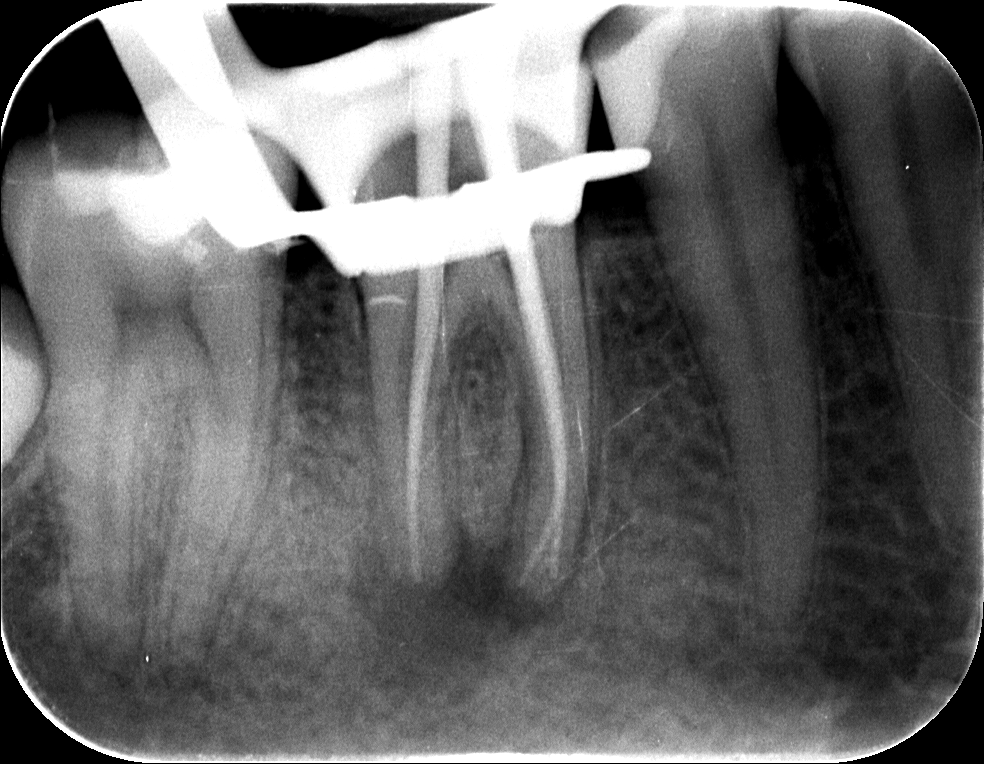

1. A kiinduló röntgenfelvétel

Dr. Kovács Kitti páciense egy három éve készült gyökértöméssel kapcsolatos panaszával kereste fel rendelőnket. A kérdéses fog az utóbbi időben bizonytalan panaszokat produkált. Néha kifejezetten fájt, néha a páciens „érezte”, hogy van foga, néha pedig teljesen panaszmentes volt.

A vizsgálatot egy kisröntgenfelvétel készítésével kezdtük, majd ezt tüzetes szájüregi vizsgálat követte. A fog kopogtatásra érzékeny volt, és a röntgenfelvételen egyértelműen látható lett a csontban lévő krónikus gyulladás (amelyet az alsó képen pirossal rajzoltunk körbe), illetve az ezt kiváltó ok, a rövid gyökértömés (amelynek hiányzó szakaszát sárgával jelöltük).